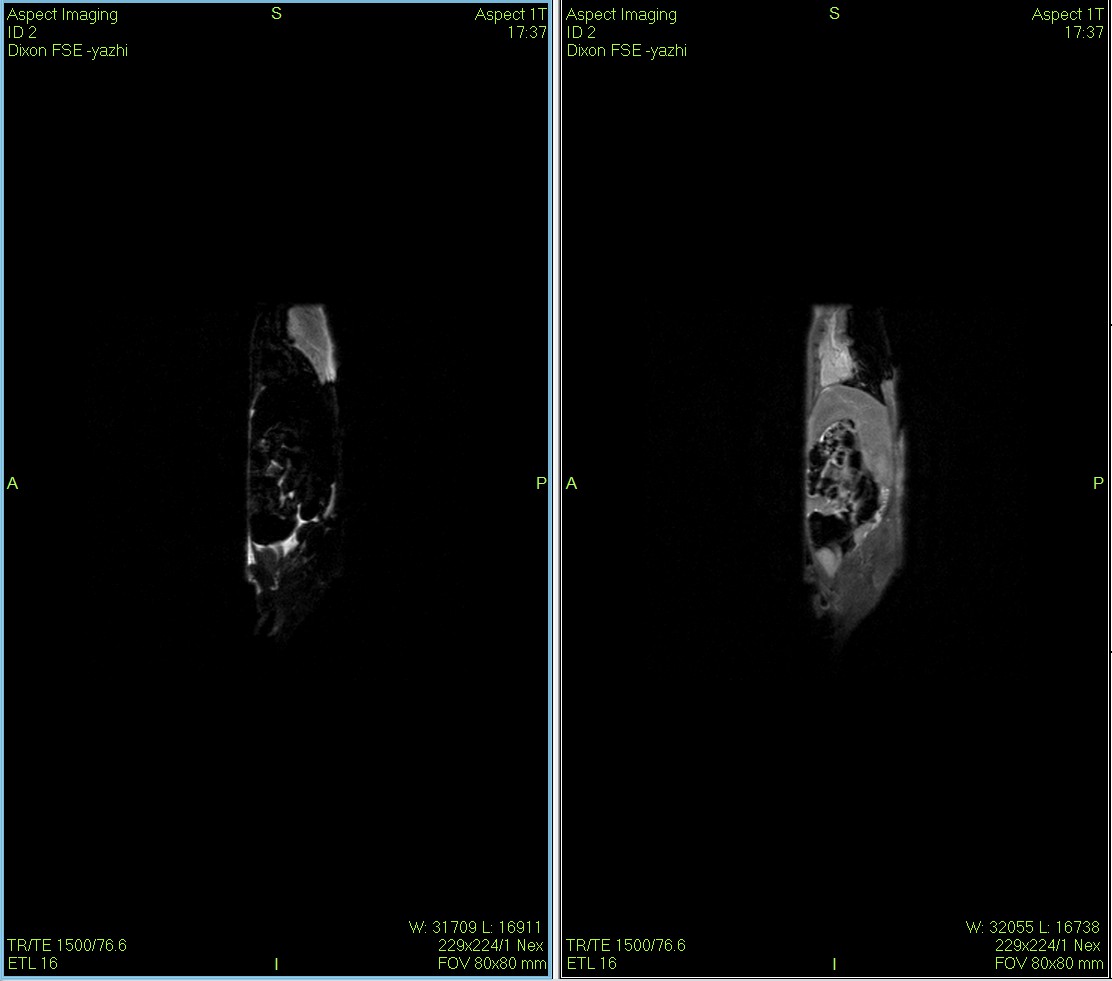

Dixon脂肪抑制技术是由Dixon 提出,其基本原理是利用水、脂肪的化学位移差异,使用不同的回波时问,分别采集水和脂肪质子的in Phase 和 opposed -phase两种回波信号。

小鼠皮下肿瘤MRI造影成像效果与造影剂代谢过程研究。